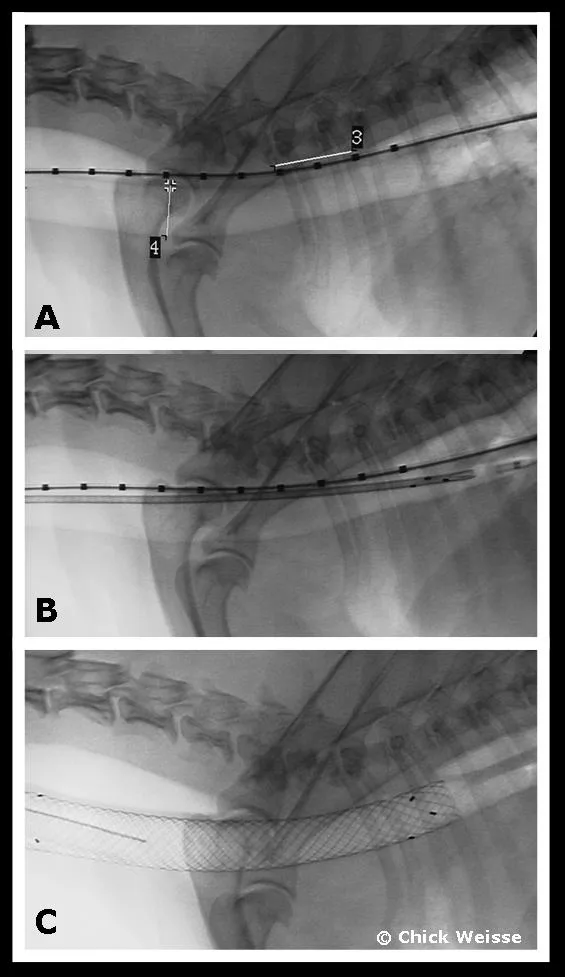

Step 4

Tracheal stent placement. Place the patient in lateral recumbency. Advance a hydrophilic guidewire and marker catheter combination down the esophagus under fluoroscopic guidance. Using positive-pressure ventilation (20 cm H2O), take a radiograph and extrapolate maximal tracheal diameter measurements using the known measurements from the esophageal marker catheter (A). Advance the delivery system and stent down the trachea (B). Withdraw the delivery sheath under fluoroscopic guidance to observe accurate placement of the stent. After complete stent deployment, remove the delivery system and take a radiograph to confirm appropriate stent placement and restored tracheal lumen (C). Postoperative care typically involves environmental oxygen enhancement if necessary as well as continued antitussive therapy (hydrocodone) and antiinflammatory agents (prednisone). Postoperative antibiotics are prescribed if a concurrent airway infection is documented or suspected.